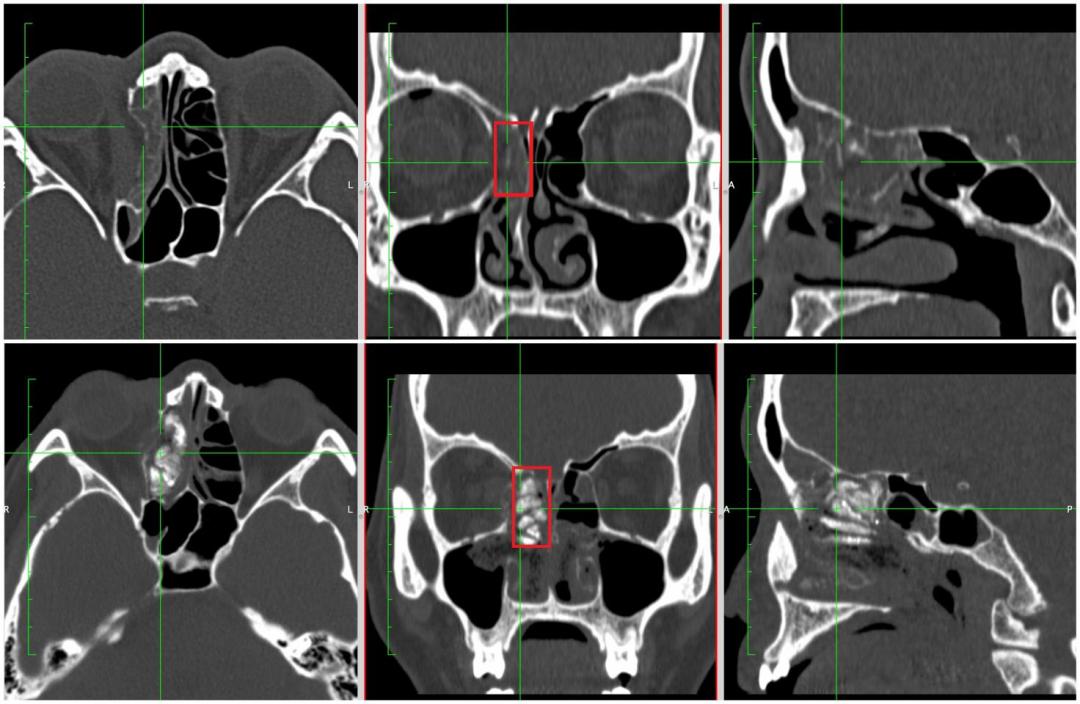

鼻内镜微创复位手术前后对比照

下图红框内为支撑物

针对刘女士的情况,吴彦桥通过鼻内镜将骨折的眶壁连同其疝入的筛窦一同复位,以粉碎的眶壁、脂肪和内直肌保护视神经,放入碘仿纱条填塞支撑,术后两个月再取出,实现了从内向外复位,避免了损伤视神经的风险,同时眼周围无手术切口,值得一提的是该手术方法利用价廉的碘纺纱进行暂时性填充,大大降低了患者的手术费用。